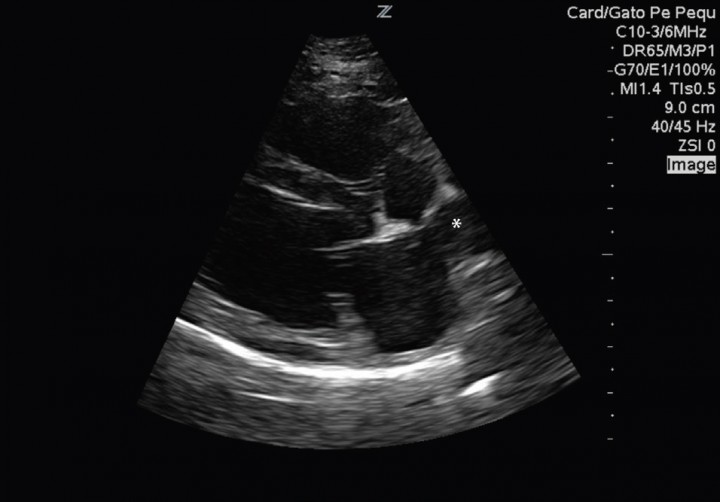

El paciente muestra disnea de tipo mixto y taquipnea (52 respiraciones por minuto). El estudio radiográfico del tórax revela la existencia de un patrón alveolar en zona perihiliar hacia lóbulos caudales compatible con edema pulmonar de tipo cardiogénico y un tamaño en el eje corte de 12 cuerpos vertebrales[ Buchanan JW, Bucheler J: Vertebral scale system to measure canine heart size in radiograms. J Am Vet Med Assoc 1995;206:194. [PubMed] ] (rango normal 9,7 +/- 0,3) (Fig. 2). Asimismo, el estudio ecocardiográfico muestra una sobrecarga de volumen ventricular izquierda, sin aumento del tamaño atrial, pero con dilatación de las venas pulmonares (Fig. 3). Las medidas ecocardiográficas muestran un aumento de la fracción de acortamiento (Fig. 4) y de eyección (VE), un ratio aorta aurícula izquierda correcto (Ratio ao/ai) y aumento del índice volumétrico telediastólico final (EDVI) (Tabla 1). No se observan alteraciones estructurales congénitas ni adquiridas.

<p>Corte paraesternal derecho eje largo, donde se observa una dilatación de la vena pulmonar (*) sin detectarse aumento del atrio izquierdo.</p>

Figura 3

Corte paraesternal derecho eje largo, donde se observa una dilatación de la vena pulmonar (*) sin detectarse aumento del atrio izquierdo.